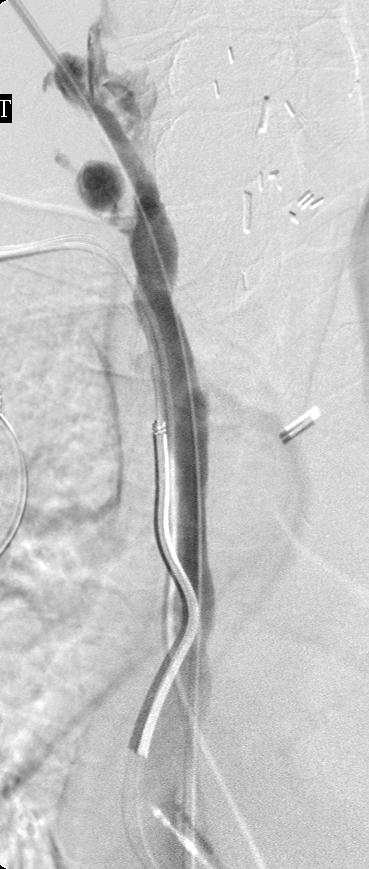

Central venogram via the REJV after track dilation: Complete restoration of luminal patency.